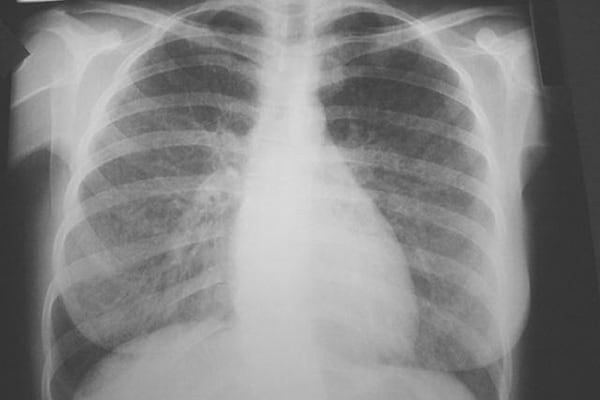

डॉक्टरों के मुताबिक निमोनाइटिस तब होता है जब कोई भी जीवाणु व्यक्ति के फेफड़ों में प्रवेश कर जाता है। इस दौरान हवा की थैलियों में सूजन होने लगती है, जिससे मरीज को सांस लेने में परेशानी, हार्ट बीट्स का तेज होने जैसी समस्या होने लगती हैं।

निमोनाइटिस फेफड़ों को होने वाला संक्रमण है, जो बैक्टीरिया, वायरस, फंगस अथवा पैरासाइट्स के कारण होता है। इसकी सबसे अहम पहचान है, फेफड़ों की वायुकोषिका में सूजन का आना या उसमें एक तरह का तरल पदार्थ का भर जाना। यह महिला और पुरुष दोनों में समान प्रभाव डालता है। कुछ वक्त पहले हुए एक शोध में यह बात सामने आई थी कि पूरे विश्व में लगभग 2 लाख से ज्यादा लोग इस बीमारी से पीड़ित है। अगर आपके मन में निमोनाइटिस को लेकर कोई भी सवाल है तो इस बारे में ज्यादा जानकारी के लिए अपने डॉक्टर या नजदीकी अस्पताल में संपर्क करें।

निमोनाइटिस मुख्य तौर पर बैक्टीरिया, वायरस या फंगल के कारण होता है। डॉक्टरों के अनुसार निमोनाइटिस का इलाज समय रहते न कराया जाए तो इससे फेफड़ों का इंफेक्शन, छाती में दर्द जैसी समस्याएं हो सकती हैं। कुछ मामलों में निमोनाइटिस के कारण मरीजों को अस्थमा की समस्या भी हो सकती है।

निमोनाइटिस का पता लगाने के लिए डॉक्टर शरीर की जांच करते हैं और मरीज की मेडिकल हिस्ट्री के बारे में विस्तार से जानकारी प्राप्त करना चाहते हैं।